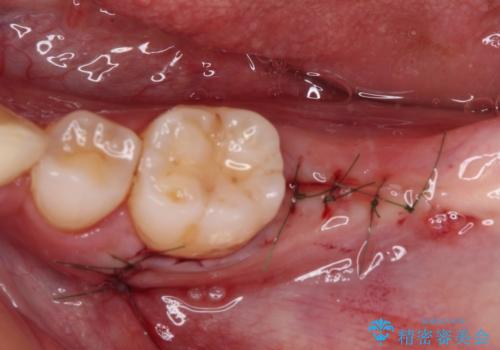

まず生活歯髄療法を行い、その後部分矯正やインプラント処置を行いましたが、最初の処置から1年以上経っても右下奥の処置歯の神経組織に異常は認められませんでした。

部分矯正を行ったことで、違和感のない咬み合わせを達成することができました。